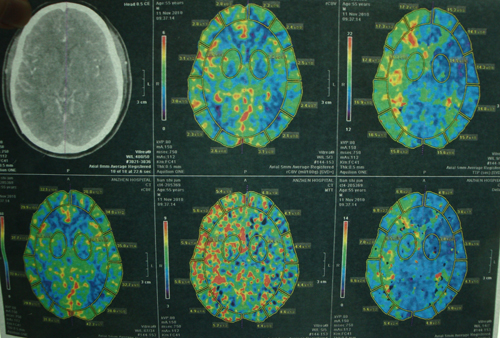

头部血管CT造影:右侧颈内动脉颅内段、右侧大脑中动脉水平段可见节段性狭窄(中度),右侧颞叶、顶叶灌注较对侧偏低。

MR示:双侧大脑半球多发腔隙性脑梗塞